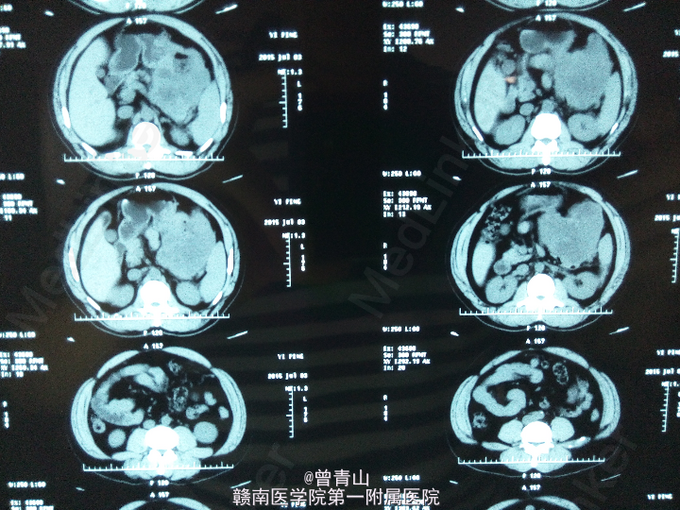

查体:腹部膨隆,软,全腹无压痛及反跳痛,左中下腹可及一大小约16.1*9.3cm的硬性肿块,活动度差,与周围组织分界不清,肝脾肋下未触及,移动性浊音阴性,肠鸣音减弱。全腹部增强CT提示:左上腹部可见一大小约10.1*15.5cm分叶状软组织肿块影,边界清楚,密度不均,增强扫描肿块不均性强化,中央可见片状无强化坏死区;肿块与胃体大弯侧关系密切,并与胃穿通,肿块内可见气液平面。电子胃镜提示:胃体占位。取活检并送病检提示:胃间质瘤。血分析:白细胞(仪器法)9.55*10^9/L,红细胞(仪器法)3.4*10^12/L。肝功能:总蛋白(双缩脲法)62.9g/L,白蛋白(溴甲酚绿法)37.2g/L,空腹血糖(酶法)7.96mmol/l。